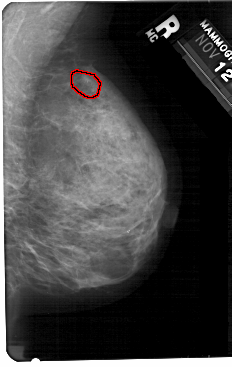

FILE: A_1367_1.RIGHT_CC.OVERLAY

TOTAL_ABNORMALITIES 1

ABNORMALITY 1

LESION_TYPE CALCIFICATION TYPE FINE_LINEAR_BRANCHING DISTRIBUTION CLUSTERED

ASSESSMENT 4

SUBTLETY 3

PATHOLOGY BENIGN

TOTAL_OUTLINES 1

BOUNDARY